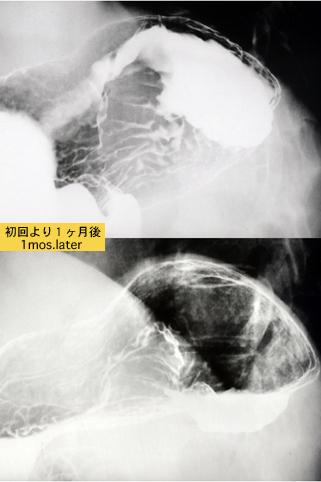

Posted by: Tokyo Pref., 国立癌中心中央病院和九州癌中心共同完成

Misc 1980-1984

疾病(病理主体)的分类肿瘤样病变/来自相邻脏器的浸润

部位(按器官分)胃(部位)/体部

检查方法X线

肿瘤最大直径40以上